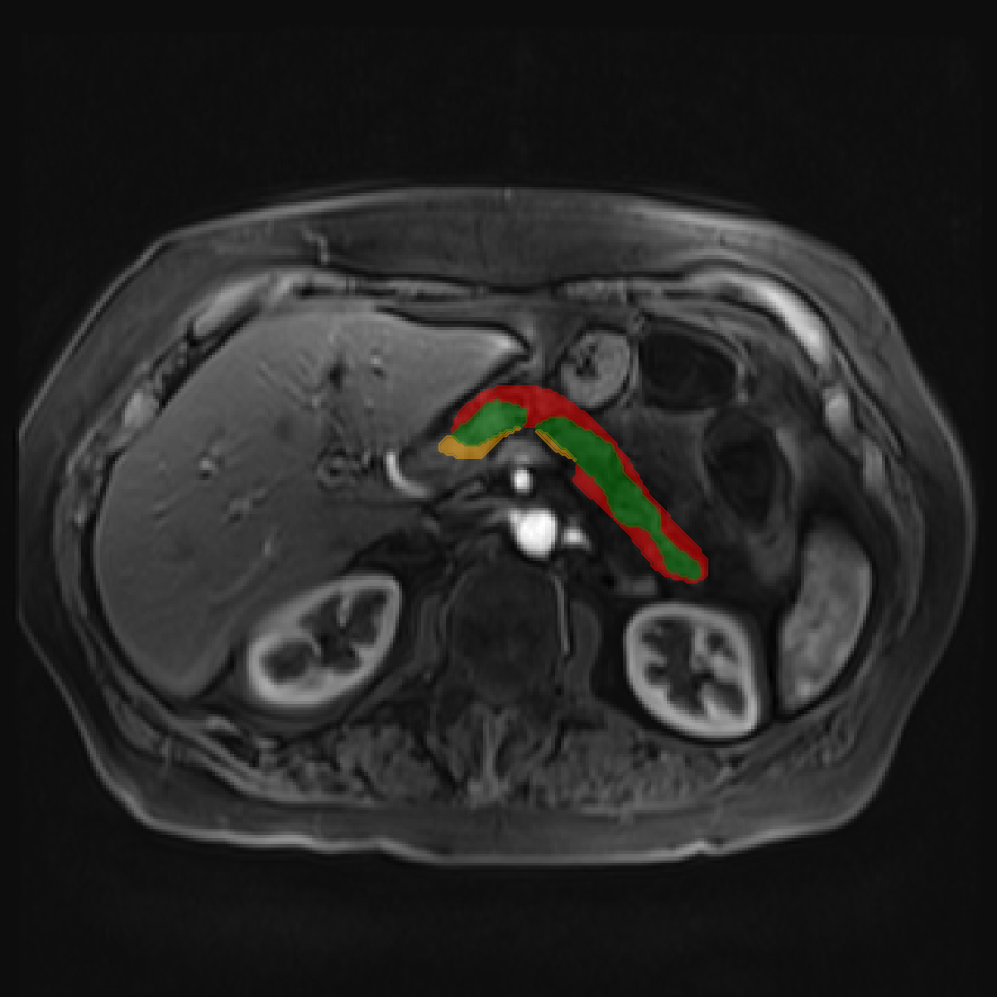

Accurate pancreas segmentation is a critical prerequisite for precise cyst analysis and classification. Recently, we developed PanSegNet [zhang2025large], a novel segmentation architecture incorporating linear self-attention layers [zhang2022dynamic] within the nnUNet framework [isensee2021nnu] to enhance global information modeling capabilities while maintaining computational efficiency (Fig. 1). PanSegNet demonstrated exceptional segmentation performance across both T1W and T2W modalities, achieving mean dice scores of 86.817.30% and 89.626.38%, respectively (Table 1, Fig. 2b-c). This performance significantly exceeded that of Swin-UNETR [hatamizadeh2021swin], one of the most used state-of-the-art transformer-based medical segmentation models, which achieved dice scores of 79.091.40% and 76.290.66% for T1W and T2W, respectively (). In this study, we integrated PanSegNet into our Cyst-X engine along with a classifier for risk prediction. In Section 2.2, we show that the choice of segmentation model affects the classification results. The performance advantage of PanSegNet was consistent across all seven medical centers, demonstrating robust generalization despite variations in imaging protocols and equipment (Table 1). This cross-institutional reliability is particularly important for clinical applications, where model performance must remain consistent regardless of imaging site or acquisition parameters.

Each patient was categorized into one of these three ground truth classes: no risk/control, IPMN low-risk, or IPMN high-risk. To evaluate variability in image acquisition, we applied uniform manifold approximation and projection (UMAP) to image quality indicators, revealing distinct clustering patterns by imaging center and slice thickness. This heterogeneity reflects real-world clinical variability, enhancing the dataset’s generalizability while presenting technical challenges for model development. Fig. 6 shows examples of low-grade, high-grade, and cancer developing IPMNs from the Cyst-X dataset.